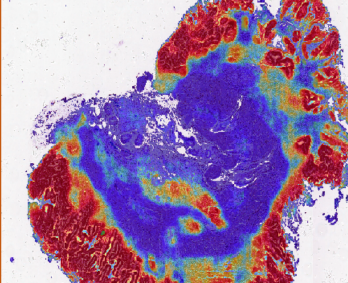

Block interception and precise amplification of gastric biopsy digital images; Tumor segmentation model

and heat map analysis; Feature extraction, negative and positive classification to predict tumor probability with high sensitivity.

2. Thermal analysis: show the risk level in each area, locate abnormal follicular cells and make an intelligent rank for quick review,

visualize each phase and one-click for online report.

3. WSI reasoning: WSI slide-window reasoning, intelligent zoom in, adenoma identification optimization.